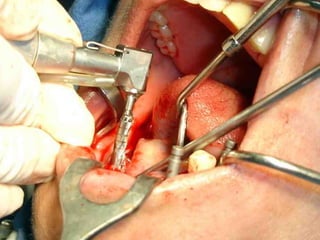

Primer tiempo quirúrgico; Exposición del maxilar para tomar una impresión del

hueso y poder elaborar la estructura implantaria.

Lingitud de hueso

Disponible 20 mm.

Implante en posición

Dejamos el implante sepultado por 4 meses previos al inicio del procedimiento

Protésico.

• Los implantes deben dejarse sin carga unLos implantes deben dejarse sin carga un

promedio aproximado de cuatro meses,promedio aproximado de cuatro meses,

después de los cuales se inicia el trabajodespués de los cuales se inicia el trabajo

protésico.protésico.

• Cuidados postoperatorios: Analgésicos,Cuidados postoperatorios: Analgésicos,